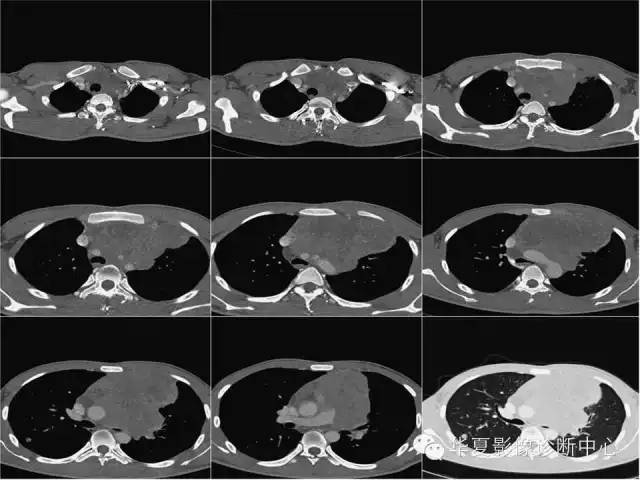

【病例】纵隔生殖细胞肿瘤1例CT影像表现